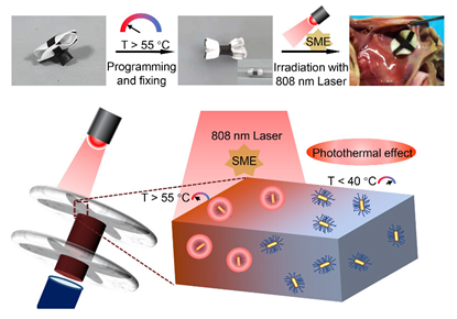

3.4. Shape Memory Biodegradable

| shape memory biodegradable [110] | NIR light-triggered shape memory effect for controlled deployment; fully biodegradable composition, using PLCL-GNR/PEG composite; maintained mechanical strength during initial tissue regeneration phase. | Long-term effects of gold nanoparticles require further study; NIR light stimulation may complicate clinical deployment procedures; primarily tested in vitro/ex vivo; needs further in vivo validation. |